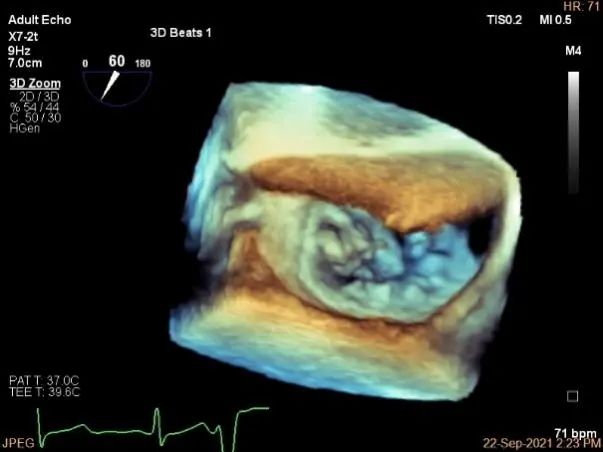

术中超声

3D:P1区脱垂并腱索断裂,Width:11.4mm

3D-color:重度MR,4级

麻醉状态下肺静脉血流频谱

MVA:7.8cm²,平均跨瓣压差:1mmHg